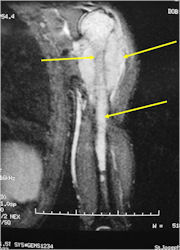

- Multiagent chemotherapy

- Most protocols administer preoperative chemotherapy then surgery is performed. Surgery is followed by several courses of postoperative chemotherapy.

- Ewing sarcoma responds well to chemotherapy. Often there is a dramatic reduction in size of the tumor.

- Soft Tissue Mass in 90% of of cases

- Lesions grossly confined to bone have a better prognosis than those with a soft tissue component

- Tumors greater than 8cm in maximum dimension and those with greater than a volume of 100cc have been associated with a worse prognosis